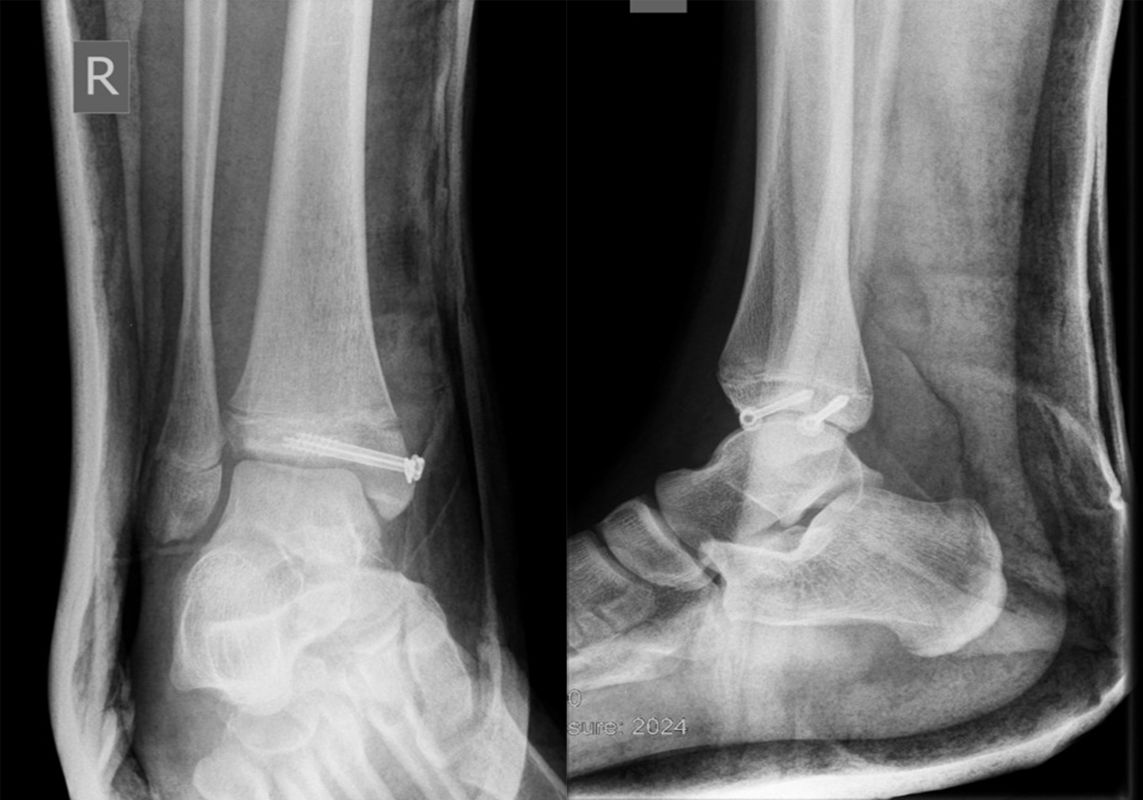

Behandlungsziel ist die exakte Rekonstruktion der Gelenkfläche sowie die Minimierung des Risikos einer späteren Wachstumsstörung. Dislozierte Frakturen werden offen reponiert, die Osteosynthese erfolgt mit einer Kleinfragmentschraube. Finden sich viele kleine Fragmente kann eine K-Draht Osteosynthese durchgeführt werden. Wird der Innenknöchel operiert, kann bei gleichzeitiger hochgradiger lateraler Instabilität eine Rekonstruktion des lateralen Bandapparats durchgeführt werden. Fibula Frakturen stellen sich meist spontan ein, sodass hier keine zusätzliche Osteosynthese notwendig ist.

Nach der Osteosynthese wird die Fraktur für ca. vier Wochen in einem Unterschenkelgips ruhiggestellt. Bei Schmerzfreiheit der Frakturzone erfolgt anschließend eine schmerzadaptierte Belastungssteigerung über weitere zwei Wochen. Sobald unter Alltagsbedingungen Beschwerdefreiheit besteht kann die sportliche Belastung langsam gesteigert werden. Kirschnerdrähte werden 6-8 Wochen postoperativ, Schrauben nach zwölf Wochen entfernt. Es empfiehlt sich klinische und radiologische Kontrollen im Abstand von 6 Monaten bis zum Wachstumsabschluss durchzuführen, um ein mögliches Fehlwachstum frühzeitig zu erkennen.